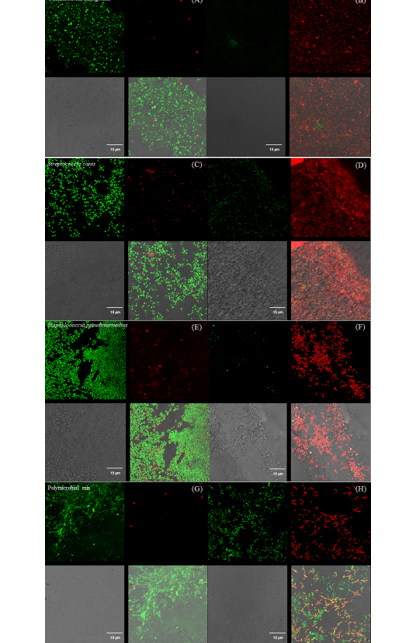

Panel with fluorescence microscope images of Pseudomonas aeruginosa (A & B), Streptococcus canis (C & D), Staphylococcus pseudintermedius (E & F), and a polymicrobial mix (G & H) inoculated superficially and treated with UV-C for 15 seconds.

Control samples are represented by images A, C, E, and G, and treated samples by images B, D, F, and H.

Each image is divided into four quadrants: the upper left quadrant shows the green channel highlighting live bacteria; the upper right shows the red channel highlighting dead bacteria; the bottom right shows the merged green and red channels highlighting live and dead bacteria; and the bottom left illustrates the bright field image. Bright green represents bacteria with intact membranes (live), red represents bacteria with compromised or dead membranes, and yellow represents bacteria with partially compromised membranes. Scale bar: 15 µm.